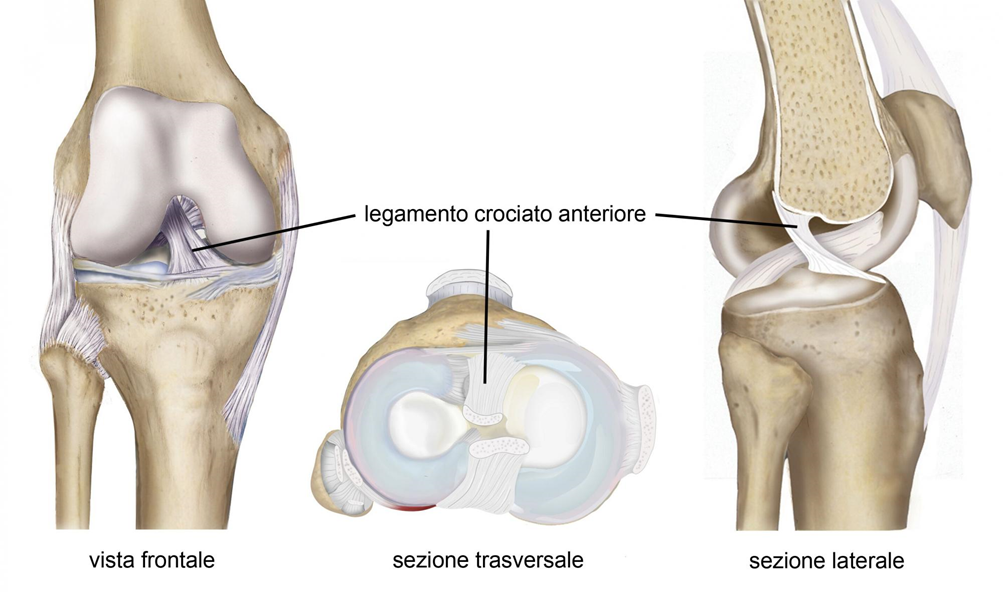

All’interno del ginocchio ci sono due legamenti che uniscono tibia e femore. Sono denominati legamenti crociati perché si incrociano al centro dell’articolazione e sono distinti in legamento crociato anteriore (LCA) e legamento crociato posteriore (LCP) (Fig. 1). Tali legamenti hanno la funzione di limitare il movimento della tibia rispetto al femore e formano il cosiddetto “pivot centrale” (centro di rotazione) del ginocchio, struttura fondamentale nel garantire la stabilità dell’articolazione.

Fig. 1 – Visione interna del ginocchio dopo rimozione dei muscoli e della capsula articolare, che evidenzia la posizione centrale del legamento crociato anteriore rispetto alle altre strutture anatomiche.